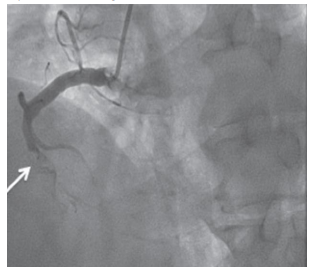

Assumindo que o achado na coronariografia (incidência oblíqua

anterior esquerda) aconteceu agudamente, sua ocorrência é

compatível com a emergência cardiovascular